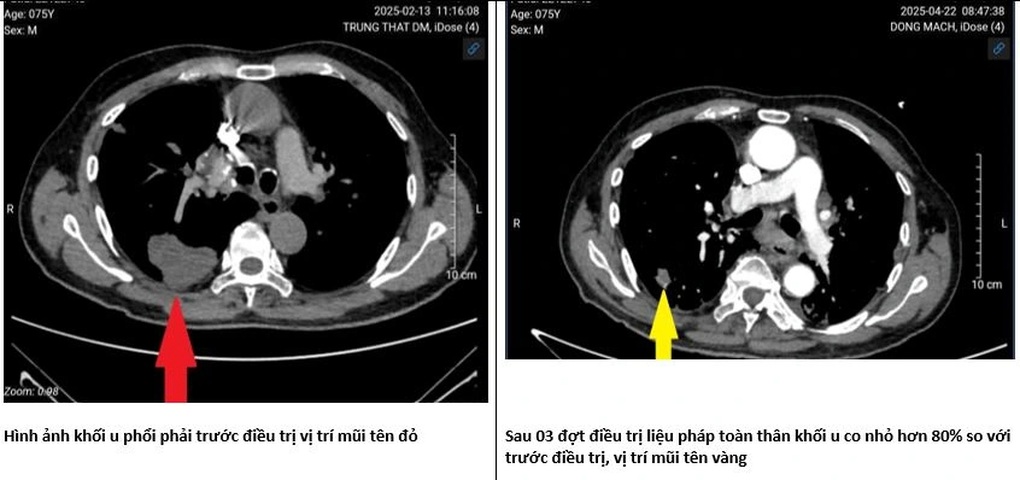

Chuyên gia này chia sẻ một trường hợp bệnh nhân 75 tuổi, mắc ung thư phổi được 3 năm.

Bệnh nhân từng trải qua phẫu thuật cắt thùy phổi chứa u nhưng đến cuối năm 2024 bệnh tái phát.

“Lúc trở lại, khối u không chỉ ở phổi mà còn lan đến các hạch cổ. Ông sút cân, mất tiếng, khó nuốt, đau nhiều và phải dùng oxy gần như cả ngày”, BS Duy Anh chia sẻ.

Thay đổi rõ rệt về kích thước khối u sau điều trị (Ảnh: Bác sĩ cung cấp).

Bệnh nhân được điều trị ban đầu bằng phác đồ phối hợp hóa chất ít độc tính và thuốc miễn dịch.

Sau chu kỳ đầu tiên, bệnh nhân đỡ đau, đỡ khó thở và không gặp tác dụng phụ đáng kể.

Khi bước vào chu kỳ thứ 4, bệnh nhân có thể nói chuyện, không cần thở oxy, ăn uống tốt hơn, và đặc biệt là sống tích cực hơn.

“Sau 3 đợt điều trị, khối u phổi phải đã tiêu biến; khối u phổi trái, các khối u vùng đáy phổi co nhỏ 50% so với trước điều trị; các hạch thượng đòn đã giảm từ 5x6cm xuống 4,5×3,5cm; thậm chí có khối u co nhỏ hơn 80% so với trước điều trị”, BS Duy Anh chia sẻ.